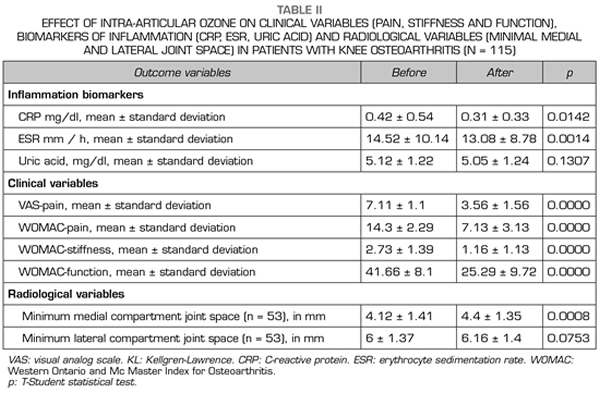

With regard to the outcome variables, the CRP and ESR inflammation biomarkers decreased significantly (p < 0.05) after ozone therapy (O2-O3). The PCR decreased from 0.42 ± 0.54 mg/dl to 0.31 ± 0.33 mg/dl (p = 0.0142) (Table II). The ESR decreased its values from 14.52 ± 10.14 mm/h to 13.08 ± 8.78 mm/h (p = 0.0014) (Table II). Serum uric acid decreased its value from 5.12 ± 1.22 mg/dl to 5.05 ± 1.24 (p = 0.1307) although this decrease was not statistically significant (Table II).

With regard to the severity of symptoms (pain, stiffness and function) in knee osteoarthritis, measured by using VAS and WOMAC scales, ozone therapy (O2-O3) significantly improved every one of the variables (p = 0.0000). Before treatment, the pain measured by VAS was 7.11 ± 1.11 points and decreased significantly to 3.56 ± 1.56 points (p = 0.0000) (Table II). Before the intervention, the WOMAC-pain subscale was 14.3 ± 2.29 points and decreased to 7.13 ± 3.13 points (p = 0.0000), the WOMAC-stiffness subscale was 2.73 ± 1.39 points and decreased to 1.16 ± 1.13 points (p = 0.0000), the WOMAC-function subscale was 41.66 ± 8.1 points and improved to 25.29 ± 9.72 points (p = 0.0000) (Table II).

Regarding the radiological variables, when evaluating 53 out of the 115 patients who completed one year of follow-up after ozone treatment, it was observed that the internal compartment increased significantly by 4.12 ± 1.41 mm to 4.4 ± 1.35 mm (p = 0.0008) and the external compartment increased from 6 ± 1.37 to 6.16 ± 1.4 mm (p = 0.0753) (Table II). Two clinical cases are presented as a sample of the radiological change in the internal and external compartments (Figures 2 and 3).